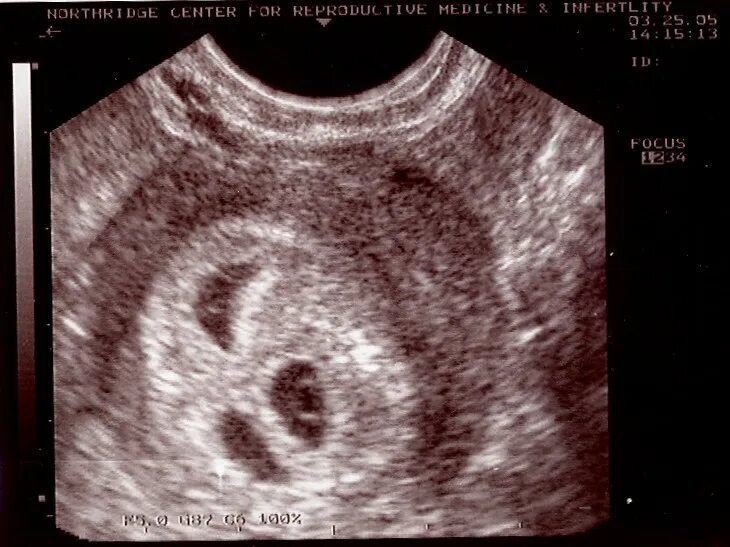

Как выглядит узи живота